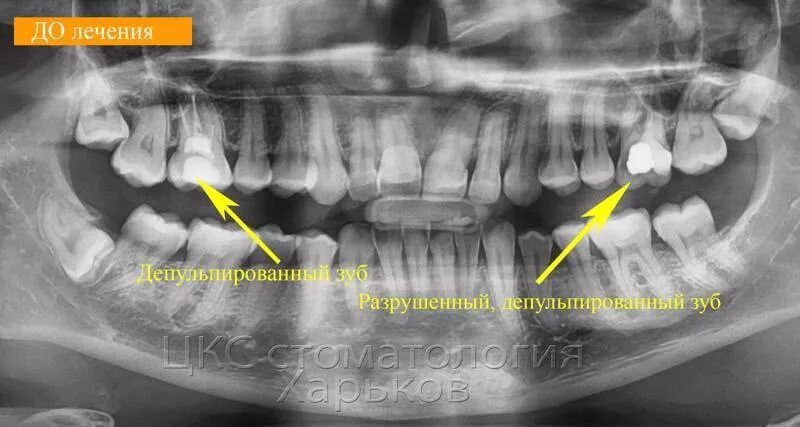

Как понять снимок зуба